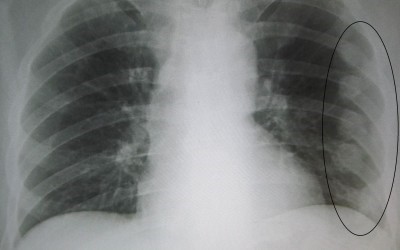

Диагноз трещина ребра врач травматолог может поставить только после медицинского осмотра. Он заключается в установке причины, определения места травмы, трещина ребра на рентгене должна быть отчетливо видна, получении послойного изображения внутренней структуры костей, наблюдении за дыханием, работой сердца и проверки общего состояния пострадавшего. Важно убедиться, что нет никаких других травм.

Во время диагностики важно определить точную травму. Часто перелом и трещина ребра имеют схожие симптомы. Перелом характерен тем, что при пальпации может слышаться хруст осколков кости, возможно смещение обломков. Важно определить точный диагноз: трещина или ушиб ребра. Точный ответ можно сказать только после проведения рентгеновского исследования. Не стоит опасаться данного назначения: вред рентгена для организма при подобном снимке ребер практически отсутствует (если, конечно, у вас нет никаких противопоказаний).

В случае, если у врача возникли подозрения на наличие осложнений, то помимо осмотра и пальпации выполняется ультразвуковое исследование органов грудной клетки и брюшной полости. Лучшим методом является рентгенография.